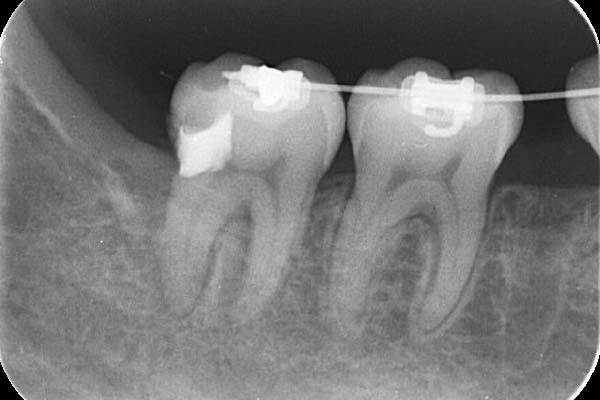

2.初診時エックス線写真

左上の1番奥の歯はすでに神経がとってあり、

大きなむし歯を認め根分岐部の歯周ポケットは8mmでした。

今回の症例では、歯根の途中にパーフォレーション(穴があいている)が認められ(黄矢印)、根の間の骨(青丸)が溶けていました(根分岐部病変)。